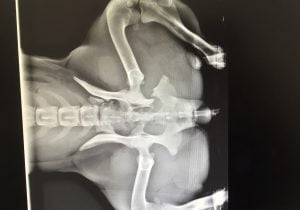

Mia’s X-rays quickly revealed multiple pelvic fractures. Fortunately, considering her clinical symptoms, surgery was not necessary and Mia’s prognosis was good. She needed to be given painkillers and had to remain immobile for a period of eight weeks to allow her fractured bones to heal. During her recovery, a few follow-up X-rays were taken to ensure that her injury was healing properly.

Keeping Mia at rest was not easy, since she’s a young dog full of energy and affection. Like most dogs her age, she always wanted to play, run and jump! It was definitely a challenge to keep her calm. Fortunately, Mia received permission from our vets to stay with a foster family while she was recovering. She was regularly brought back to the SPCA for medical follow-ups and x-rays.

During her last visit, Mia and her foster family received excellent news: Mia’s pelvis was setting nicely. Mia is now being guided through daily physiotherapy exercises so that she can completely recover. She will soon be looking for a permanent home to call her own, where she can continue to receive proper follow-up care.